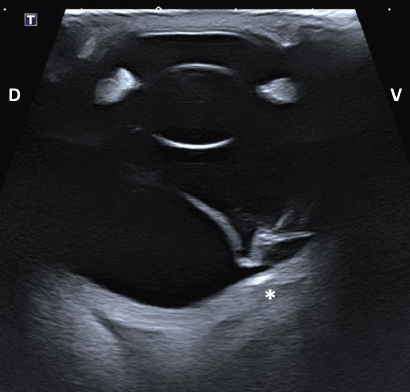

Intraocular lesions found on US and MRI of both horses were consistent with the ophthalmic examination. Complete RD OS and hyperechoic vitreous floaters OU were noted on US (Fig. 4). RD was also evident OS on MRI, more conspicuously on T2W and FLAIR sequences. In T2 sequences, the detached retina was identified as a V-shaped membrane of intermediate signal inside the hyperintense vitreous and reaching the optic disk (Fig. 5A), while it was slightly hyperintense in comparison to the hypointense vitreous chamber on FLAIR acquisitions (Fig. 5B). There was a subjectively abnormal positioned optic disk OU on US and MRI, suggesting ectopic ONH. OS was flattened at the level of the ONH in both horses. Except for a subarachnoid emphysema due to postmortem changes, the brain looked otherwise normal on MRI. Based on US, the axial globe length measured 39.2 mm OS and 41.5 mm OD of case 1 and 45 mm OU in case 2.

Fig. 4. Transpalpebral ultrasonographic image OS of case 1 in a vertical longitudinal axis. A “seagull sign” is visible in the vitreous, consistent with RD. * Note the depression at the caudoventral aspect of the globe, in the area of the optic disk (not visible on this isolated image). D: dorsal; V: ventral.